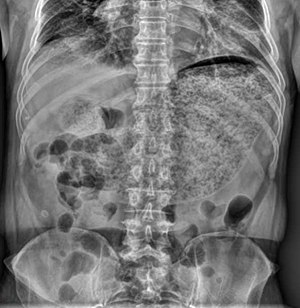

Gastroparesis can be diagnosed with tests such as barium swallow X-rays, manometry, and gastric emptying scans.[30] For the X-ray, the patient drinks a liquid containing barium after fasting which will show up in the X-ray and the physician is able to see if there is still food in the stomach as well. This can be an easy way to identify whether the patient has delayed emptying of the stomach.[31] The clinical definition for gastroparesis is based solely on the emptying time of the stomach (and not on other symptoms), and severity of symptoms does not necessarily correlate with the severity of gastroparesis. Therefore, some patients may have marked gastroparesis with few, if any, serious complications.[citation needed]

In other cases or if the X-ray is inconclusive, the physician may have the patient eat a meal of toast, water, and eggs containing a radioactive isotope so they can watch as it is digested and see how slowly the digestive tract is moving. This can be helpful for diagnosing patients who are able to digest liquids but not solid foods.[31]